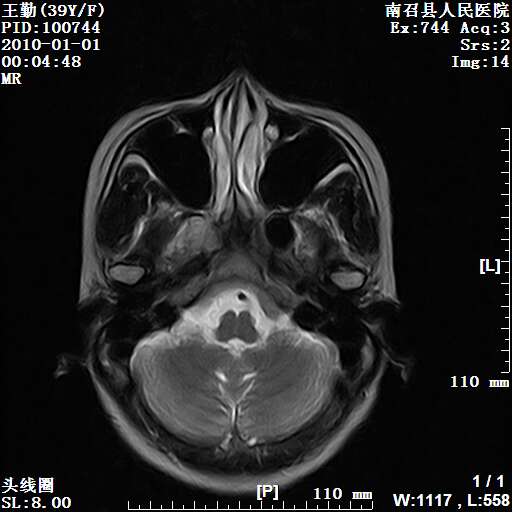

以下是引用随光逐影在2010-1-22 9:03:00的发言:[br]考虑左侧中颅窝(蝶骨翼区)脑膜瘤侵犯蝶骨翼并突入左侧眼眶。

以下是引用水过无痕在2010-1-22 14:55:00的发言:[br]一、定位:颅外占位;二、定性:恶性可能性大;三、组织来源:来源于左侧眼外直肌或其他部位;考虑为:横纹肌肉瘤>转移瘤>脑膜瘤.